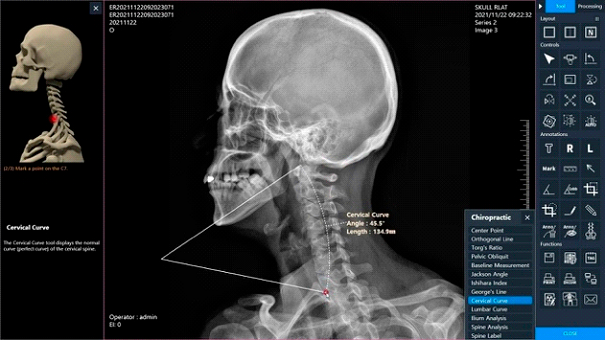

At W Med Solutions, we understand that chiropractors need more than just clear images — they need tools designed specifically for spinal analysis, patient education, and efficient workflow. That’s why we created ExamVue Chiropractic, an advanced digital radiography solution built to meet the unique demands of chiropractic practices.

With powerful imaging software, precision chiropractic measurement tools, and seamless integration into your clinic’s workflow, ExamVue makes it simple to capture, analyze, and share high-quality digital X-rays. From full-spine stitching to specialized angle measurements, ExamVue gives chiropractors the accuracy and confidence needed to deliver exceptional care while improving efficiency and patient experience.